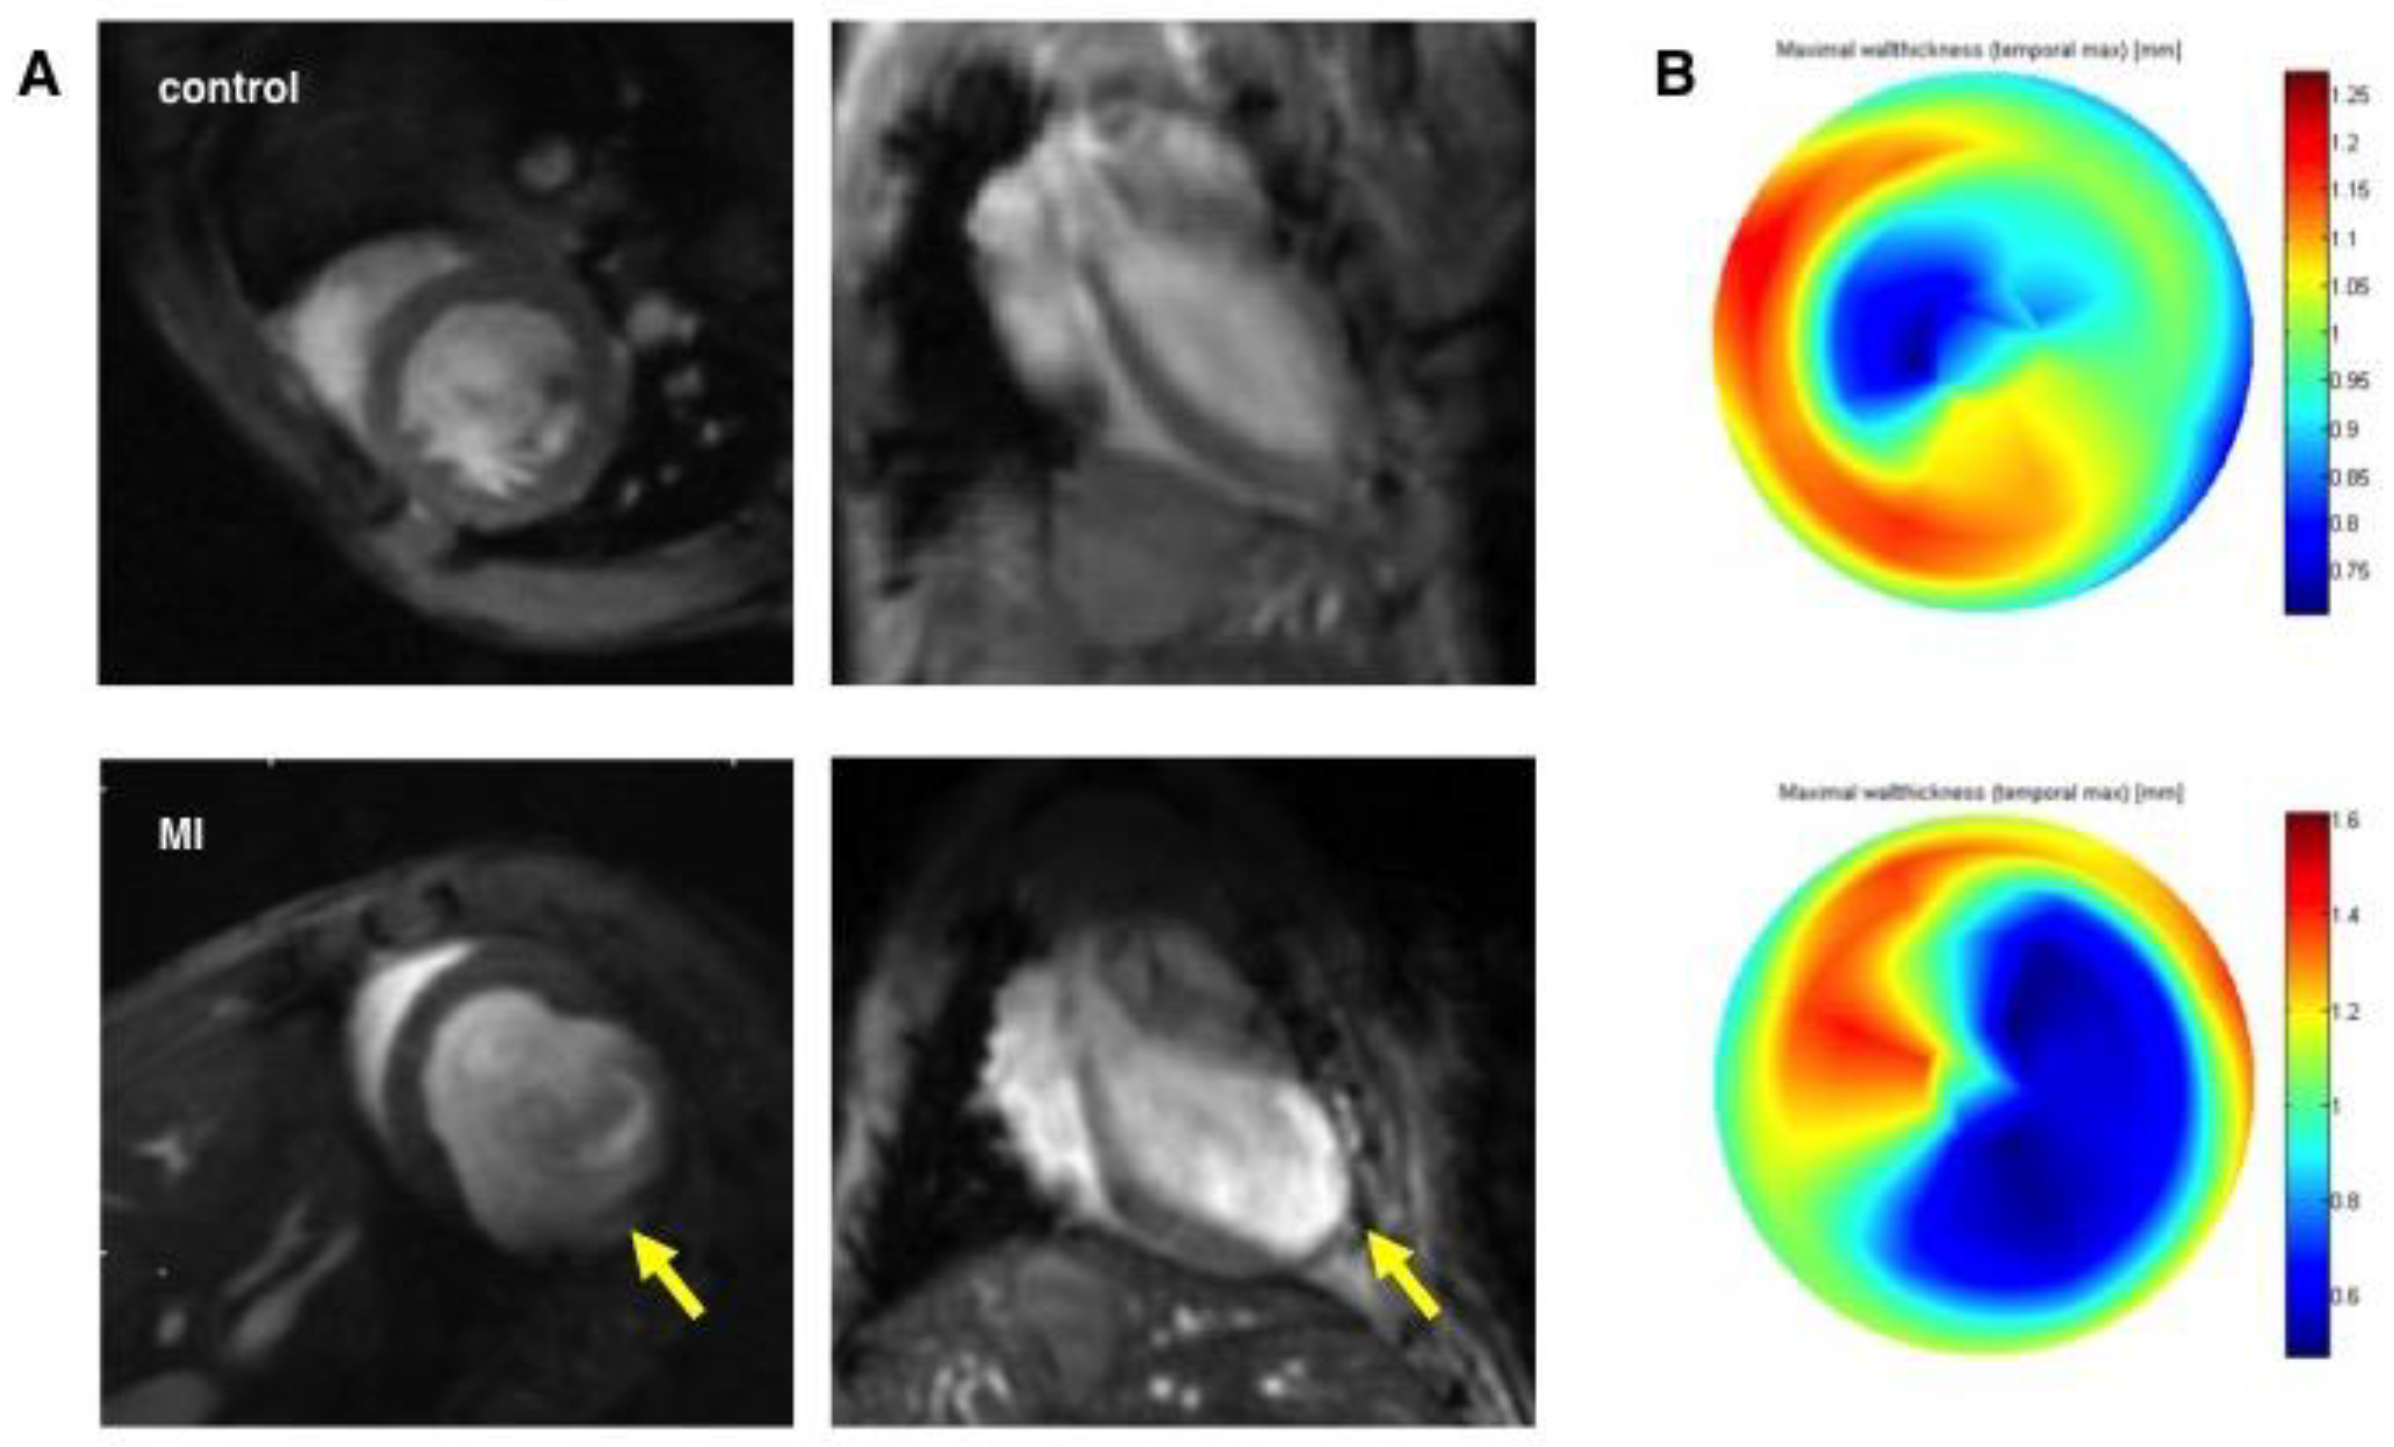

3.2. Assessment of Left Ventricular Remodeling Following AMI by the Use of MRI